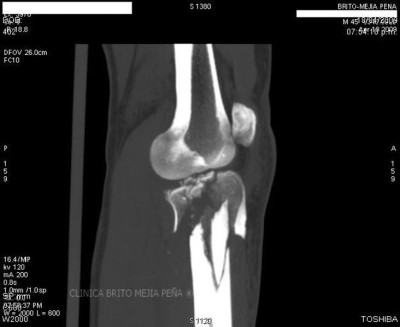

Fractura tibia MPR